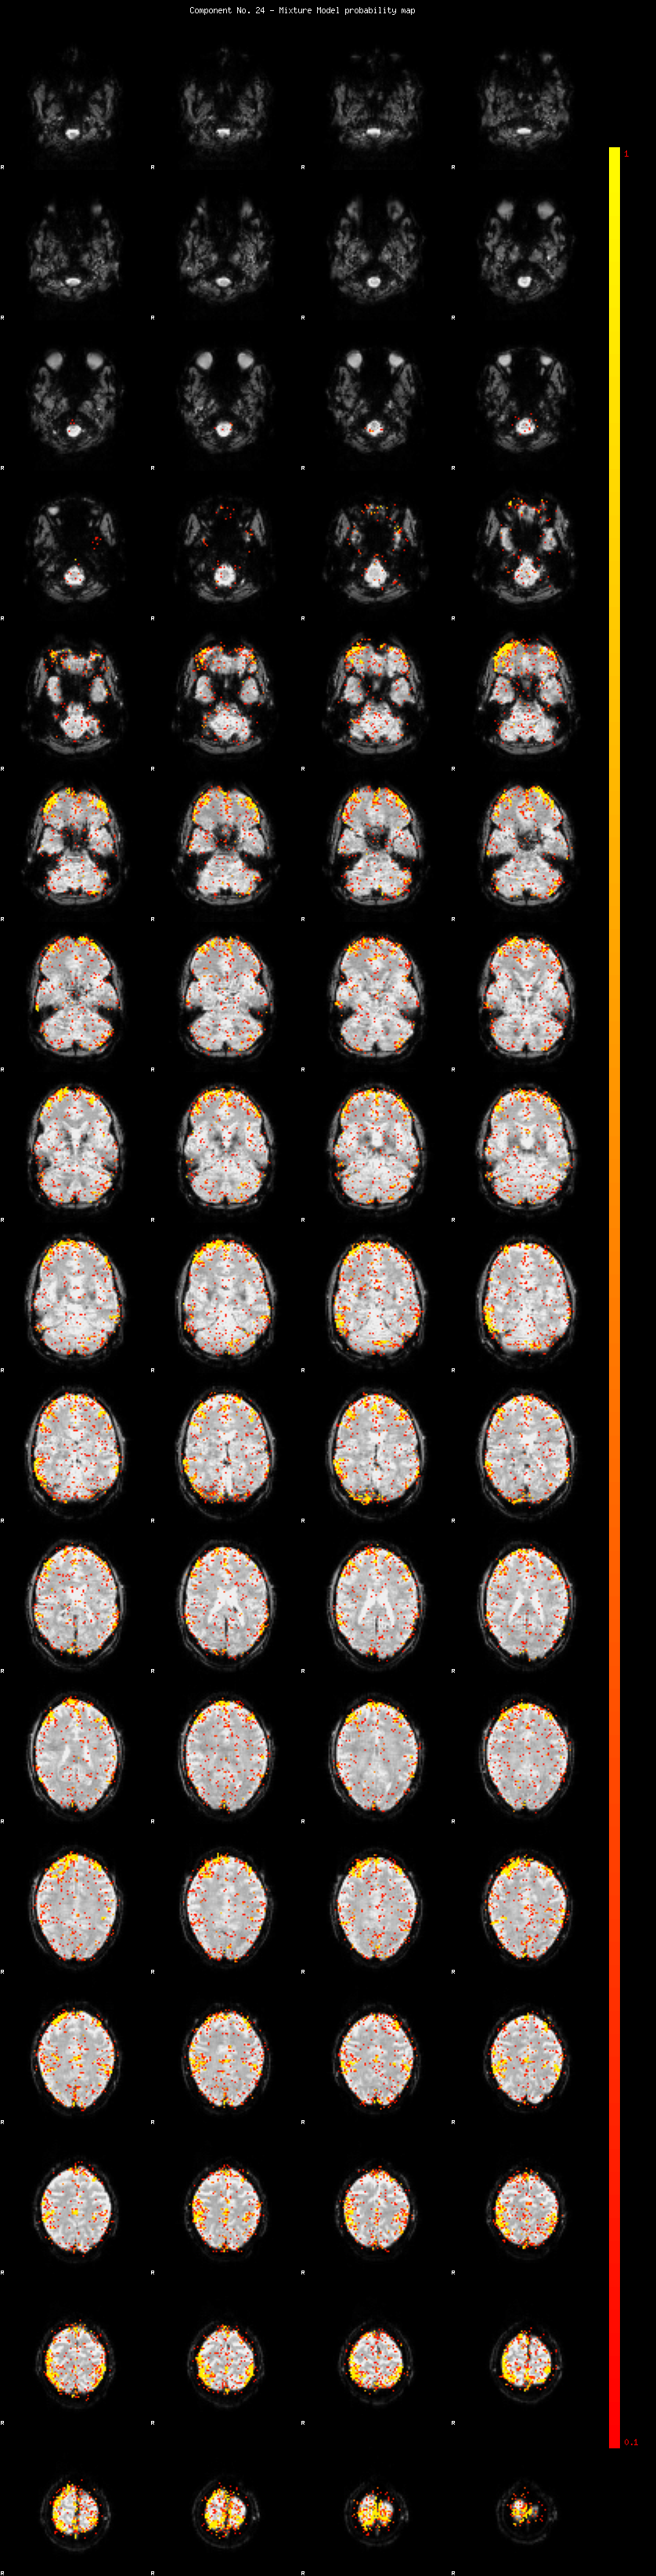

IC_24 Mixture Model fit

Means : 0.000000 4.005673 -2.660958

Vars : 1.000000 7.365442 1.481177

Prop. : 0.933162 0.049638 0.017200